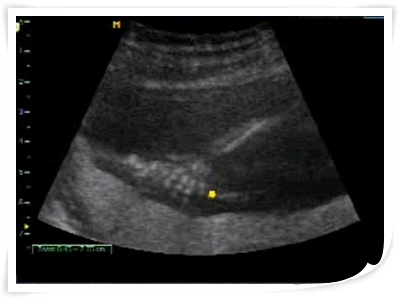

2011.01.29.토 -16주4일- 강이손~찍히다

강아~ 어제 우리 강이가 왕자님이라는 사실을 알았단다~

선생님과 엄마 아빠가 강이 심장소리 좀 듣겠다는데

빙그르르~ 돌면서 아주 활발하게 놀아준 덕에 엄마는 이상한 심장소리에

우리 강이 정밀초음파는 3월7일 월요일 오후에 볼꺼야~